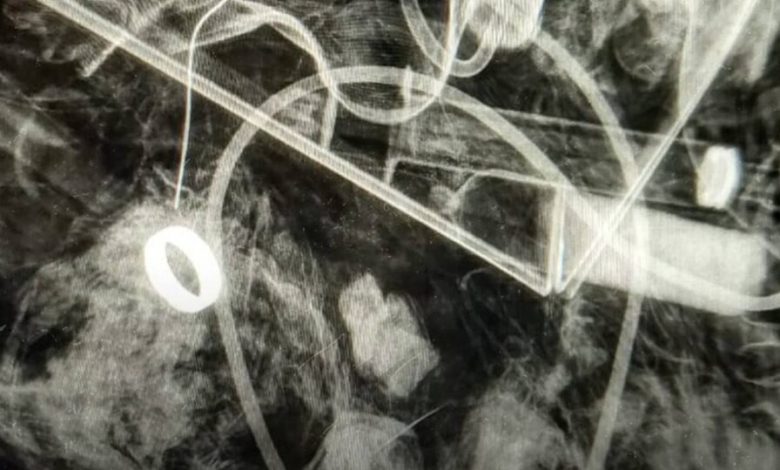

У пошуку рішення, хтось із колег запропонував просвітити сміттєвий пакет… в рентгені!

— Це ж геніально! Пішли! Сміття на рентгені в нас ще не було!

Перший же знімок — обручка там! Нові пошуки — безуспішно.

Знову знімок! Обручка точно була в пакеті. Знову перебирання пелюшок, бинтів, розкриття всіх термоковдр — і ось, вона нарешті в руках наших медиків.

А наших медиків тепер розважає історія про сміттєвий пакет під променями рентгену», — розповіли в батальйоні.